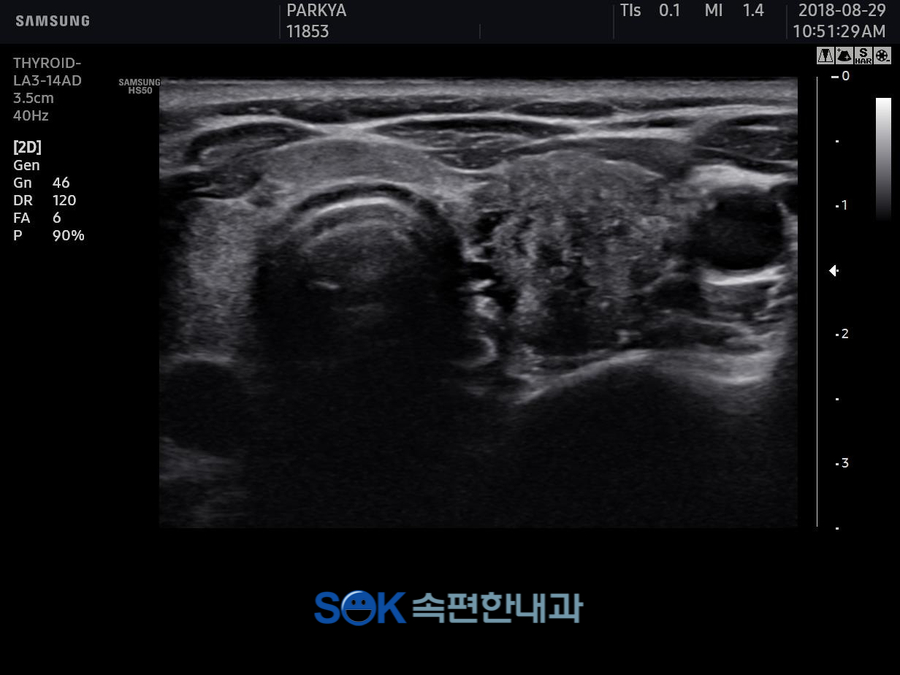

먼저 초음파 공주갑상선 검사로 설명드리면 초음파를 이용하여 갑상선의 형태와 인근 조직까지 파악하는 용도로 사용되었습니다.

이를 통해 알 수 있는 병증으로는 결절이 있지만 결절이 모두 좋지 않은 방향으로 영향을 미치는 것은 아니었어요.

2밀리미터 이내의 크기까지 확인되어도 경과를 추적하고 있으면 아무런 문제를 일으키지 않는 것을 확인할 때도 있었습니다.

이런 결절은 굳이 떼어내지 않아도 된다고 말씀드릴 수 있는데요. 실제로 40% 정도는 섬세한 결절을 가지고 있다고 생각해 주시기 바랍니다.

그 이외에 점점 커지는 경우나, 작업원 조직을 침해하는 경우는 제거하는 것을 생각할 필요가 있었습니다.